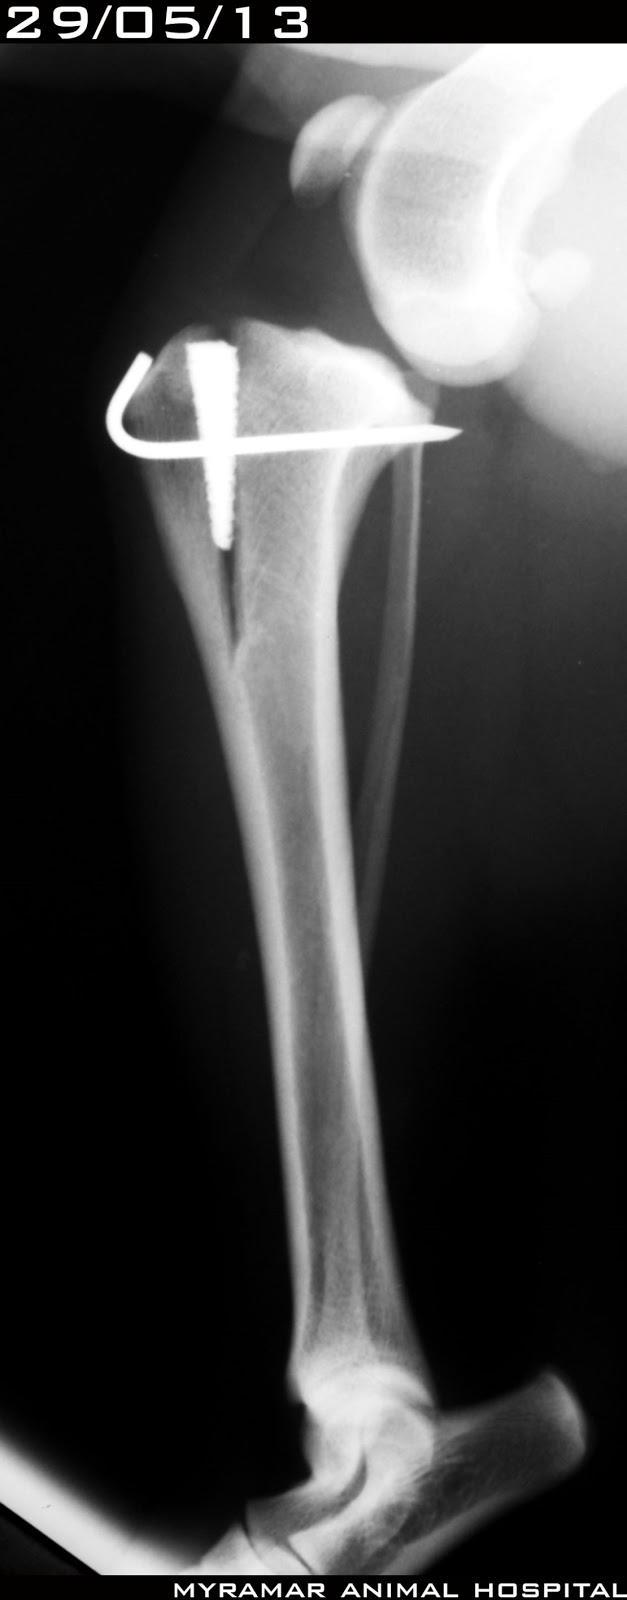

Milú, cruce de 9 años y 12 kg de peso, llega a consulta con rotura de ligamento cruzado anterior izquierdo.

Se realiza MMP (técnica modificada de maquet) realizando avance de 5mm con cuña de titanio poroso (orthomed) y K-wire de 1.6mm.

Se realiza corte largo de cortical craneal de tibia y se deja sin banda de tensión.

Se presentan radiografías pre y postquirúrgicas del caso así como evolución en el tiempo.